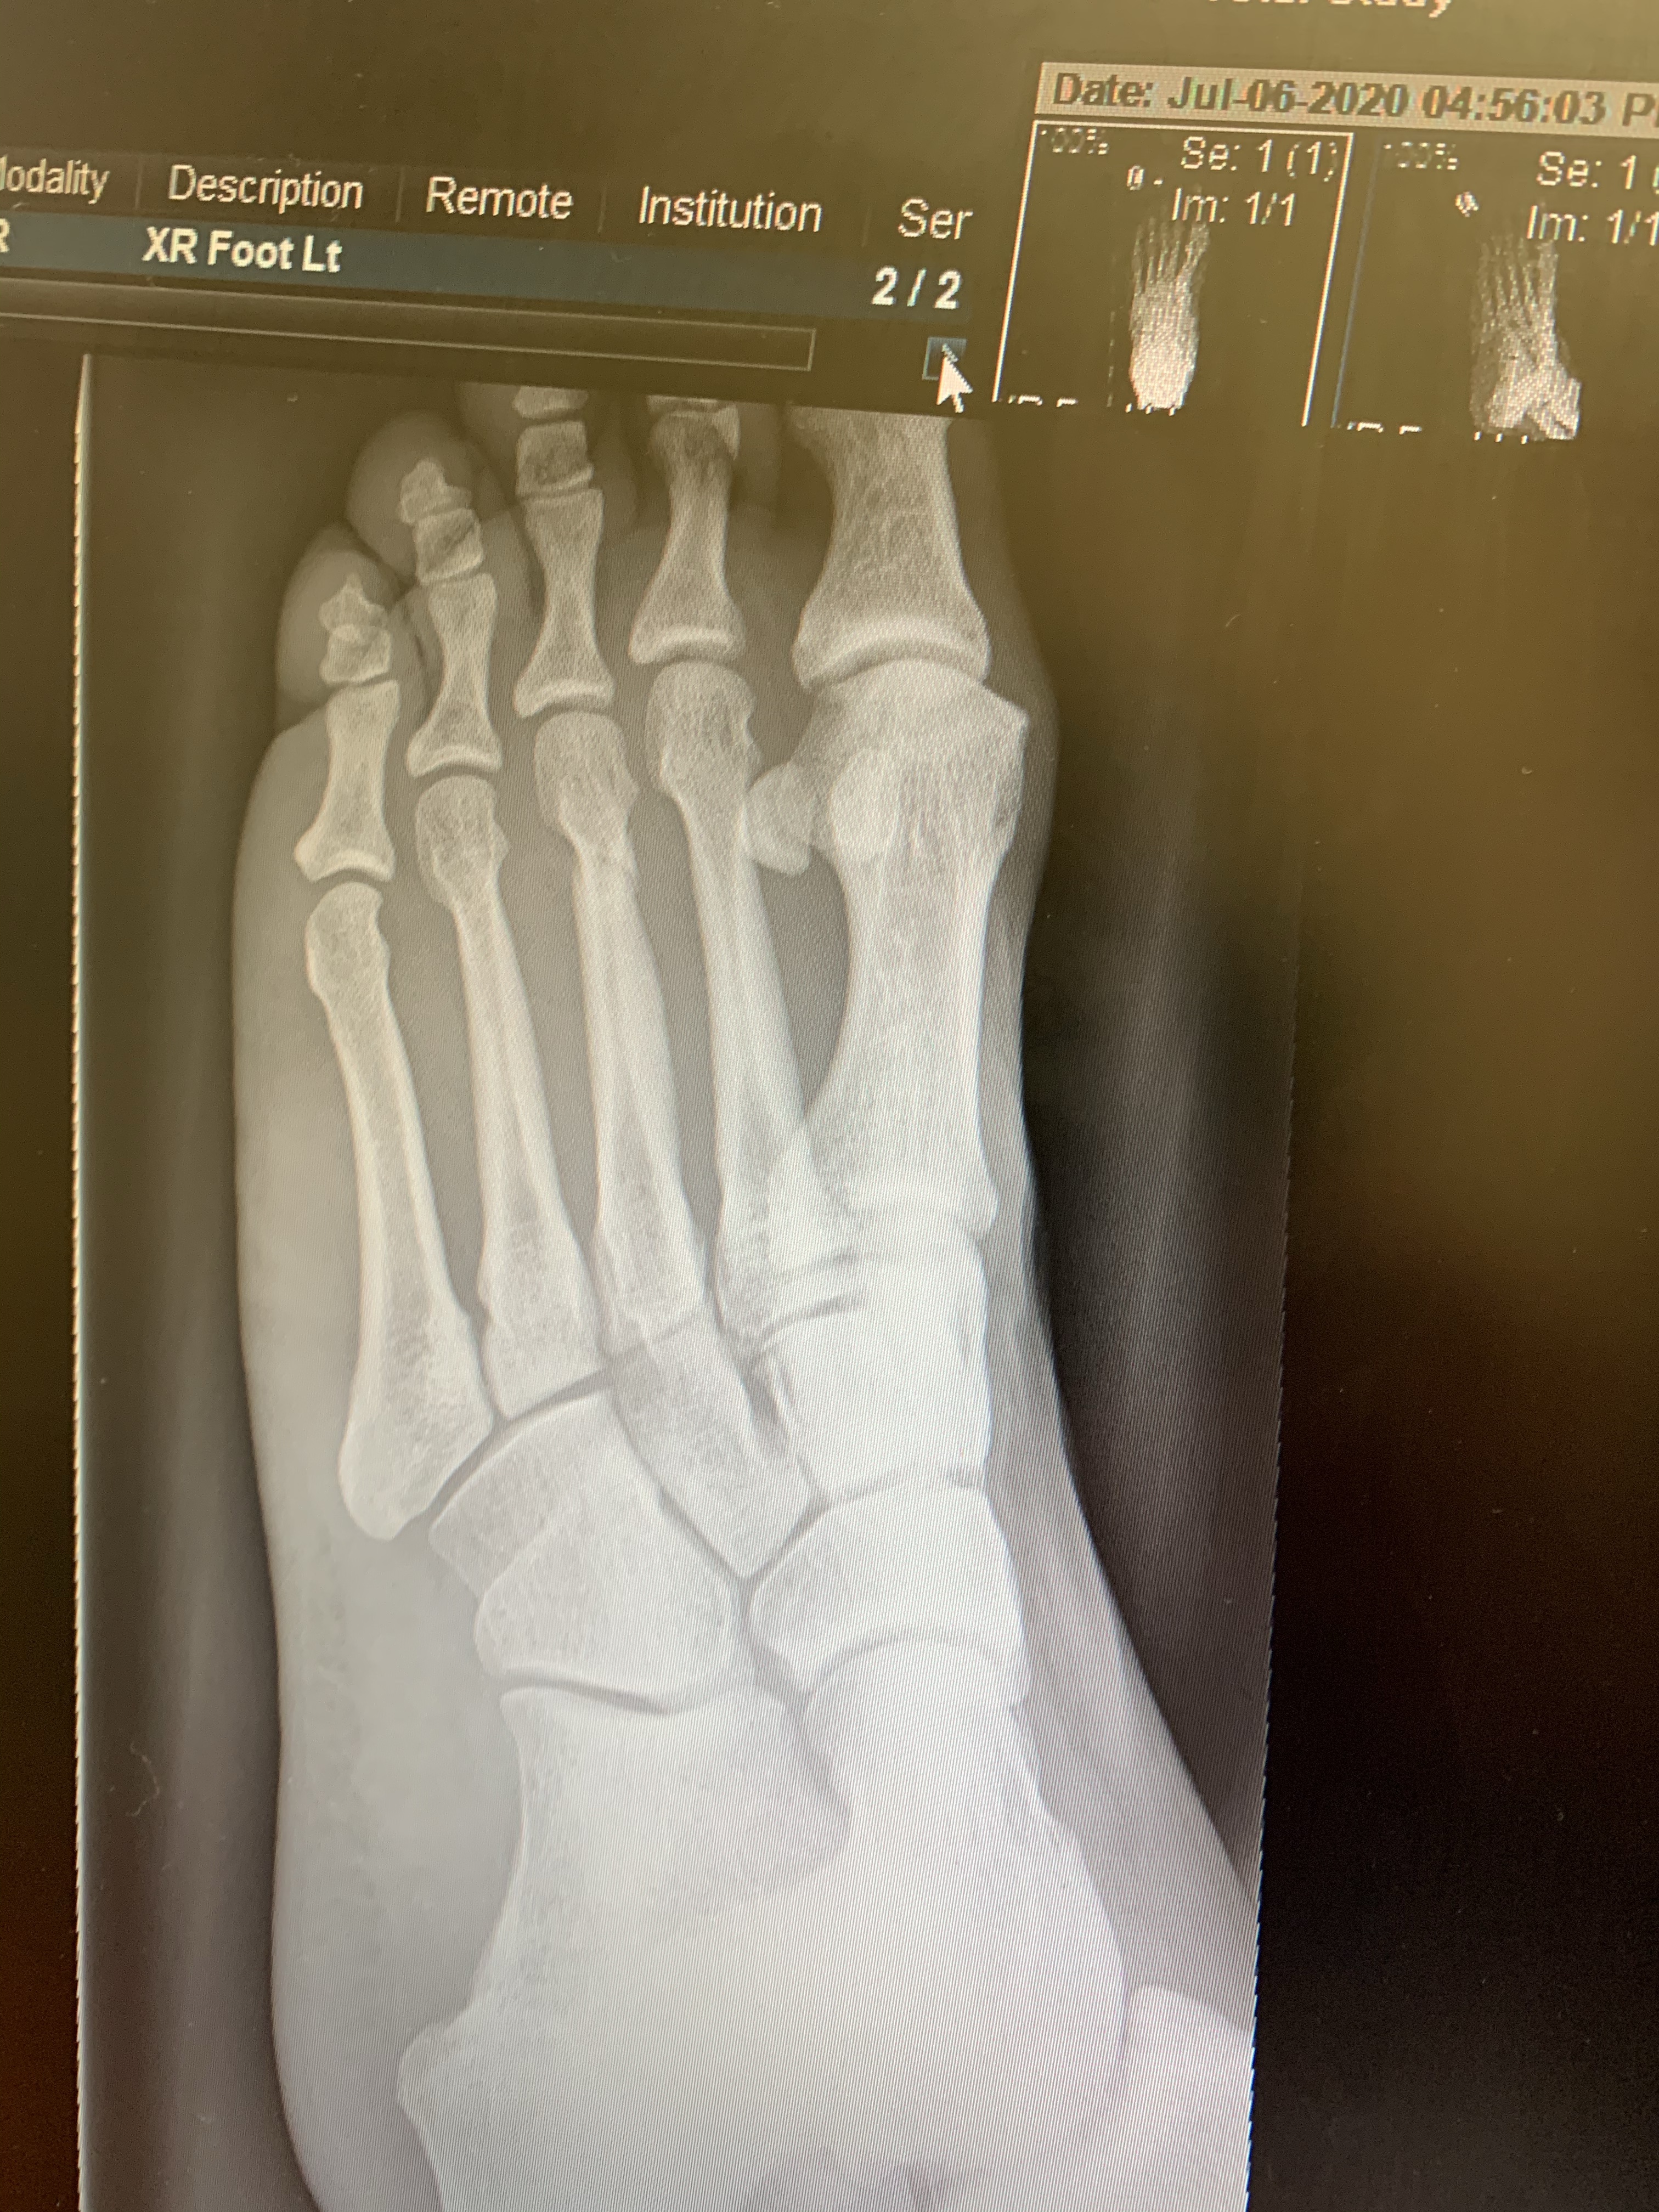

2 weeks ago sadly I suffered a minor stress fracture in my left foot 😦

Couldn’t walk very well on it. Think if my work didn’t send me home I probably wouldn’t have gone to A and E to get this checked out.

It came on on my 17 mile long run, and had company on this run to Holly Haywood came with me for the last 7 miles, and in the final ; miles my foot really hurt, but I kept going and made it back to the car, as soon as I stopped it really hurt and stiffened up.

So where am I now ?! I’m using my bike to keep my cardio going I’m averaging 15-17miles per day, longest ride is 20 miles.